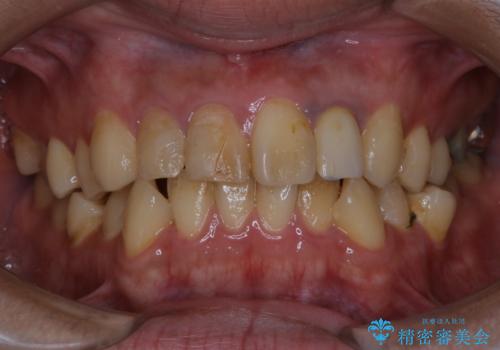

歯の表面に、茶色く色が残っている所がありますが、これは詰め物の変色の所と、虫歯になっている所です。以前に、CR(コンポジットレジン)による虫歯治療がされています。

CRは経年的劣化や、着色してしまうことがあります。PMTCでクリーニングを行うと、古いCRが目立つことがあるため、気になる際は詰め替えを行います。

茶色くなっている部分が、着色なのか、劣化なのか、虫歯によるものなのかは判別が難しいことがあります。そのため、定期的にPMTCを行うことで状態の確認が的確に行えます。